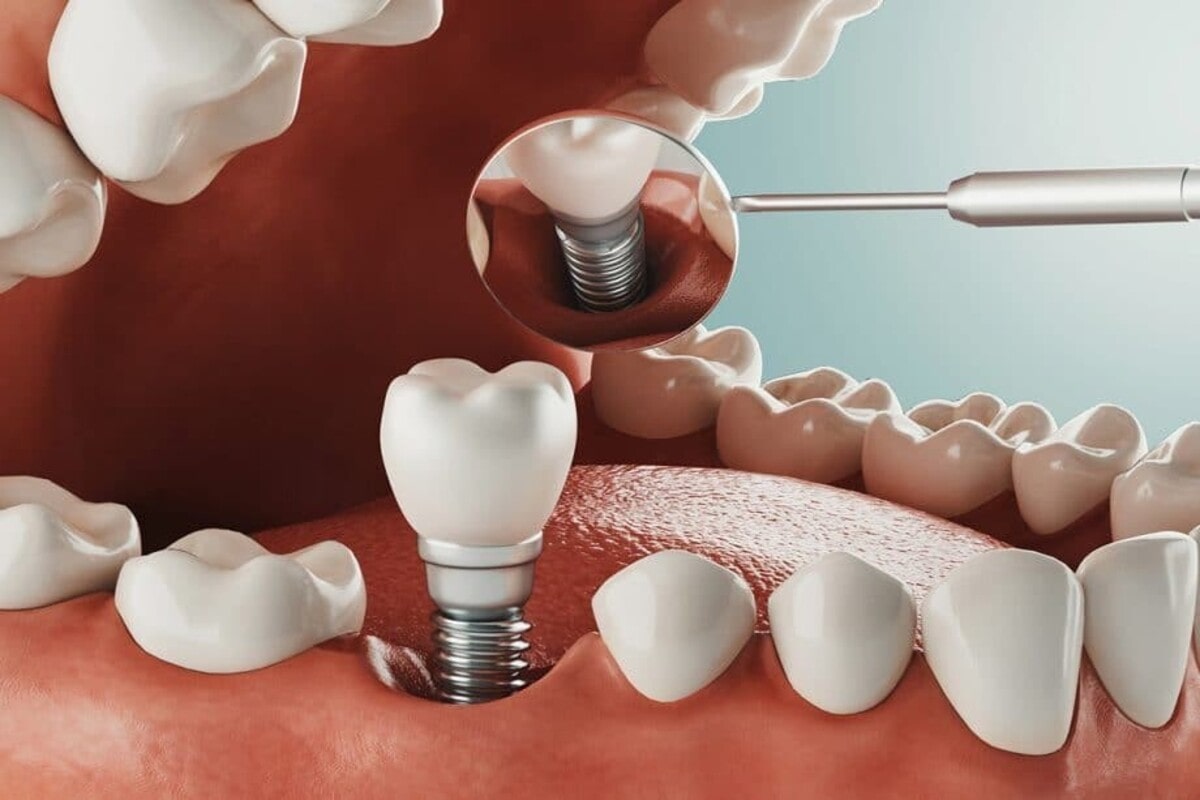

فقدان یکی یا چند تا از دندانها شرایط بدی را برای فرد ایجاد میکند. جای خالی دندان از دست رفته هم زیبایی لبخند را کم میکند و هم از طرف دیگر مشکلاتی از قبیل نامرتبی دیگر دندانها را به همراه دارد. کاشت ایمپلنت دندان جزو درمانهای طولانی در دندانپزشکی محسوب میشود و حداقل 8 ماه طول میکشد. با این حال در روش کاشت ایمپلنت یک مرحله ای، همه مراحل ایمپلنت تنها در یک جلسه انجام میشوند و طول دوره درمان به حداقل ممکن میرسد. در ادامه این مطلب میخواهیم در مورد جراحی ایمپلنت دندان یک مرحله ای و دو مرحله ای چیست توضیح دهیم. با ما همراه باشید.

کاشت ایمپلنت فوری یا یک مرحله ای، روشی است که در آن کشیدن دندان قبلی و نصب پایه ایمپلنت همگی در یک جلسه انجام میشوند. یعنی در همان روزی که ریشه دندان یا خود دندان از دهان خارج میشود، بلافاصله پایه ایمپلنت درون استخوان فک نصب میشود.

منظور از کاشت ایمپلنت دو مرحله ای، همان روش متداول کاشت ایمپلنت است که نصب ایمپلنت در دو مرحله جراحی انجام میشود. طول دوره درمان در ایمپلنت دو مرحله ای بیشتر از ایمپلنت یک مرحله ای است و طبق مراحل زیر انجام میشود:

- نصب پایه ایمپلنت

- نصب اباتمنت

- نصب روکش ایمپلنت